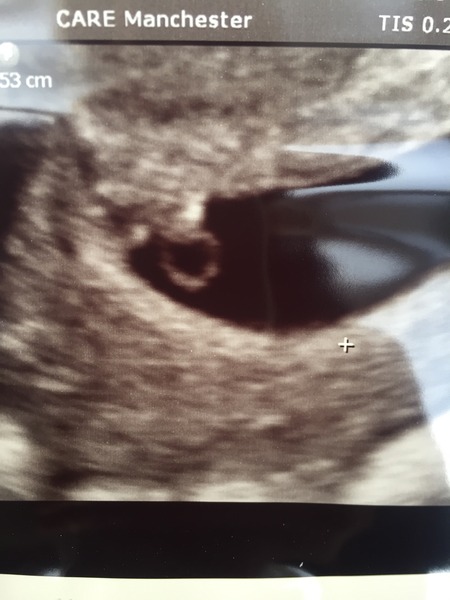

Hello ladies hope your not feeling too rough! I had a six week scan this morning and it's got a tiny little heartbeat Grin

Lovely scan picture Chocolate.

Oh wow a scan picture already! How cute! Only 2 weeks until my early scan, can't wait although extremely nervous.

Thanks guys it's through IVF so I get to have a peek early.

Wow how lovely chocolate! Seriously considering going private for a scan as got 7 weeks til nhs one and 5 weeks til booking in apt Sad (I thought it was going to be 8 weeks for bloods but they changed their minds again!) All too far away! Just got to see what dh thinks about paying privately ...

chocolate your scan is amazing!